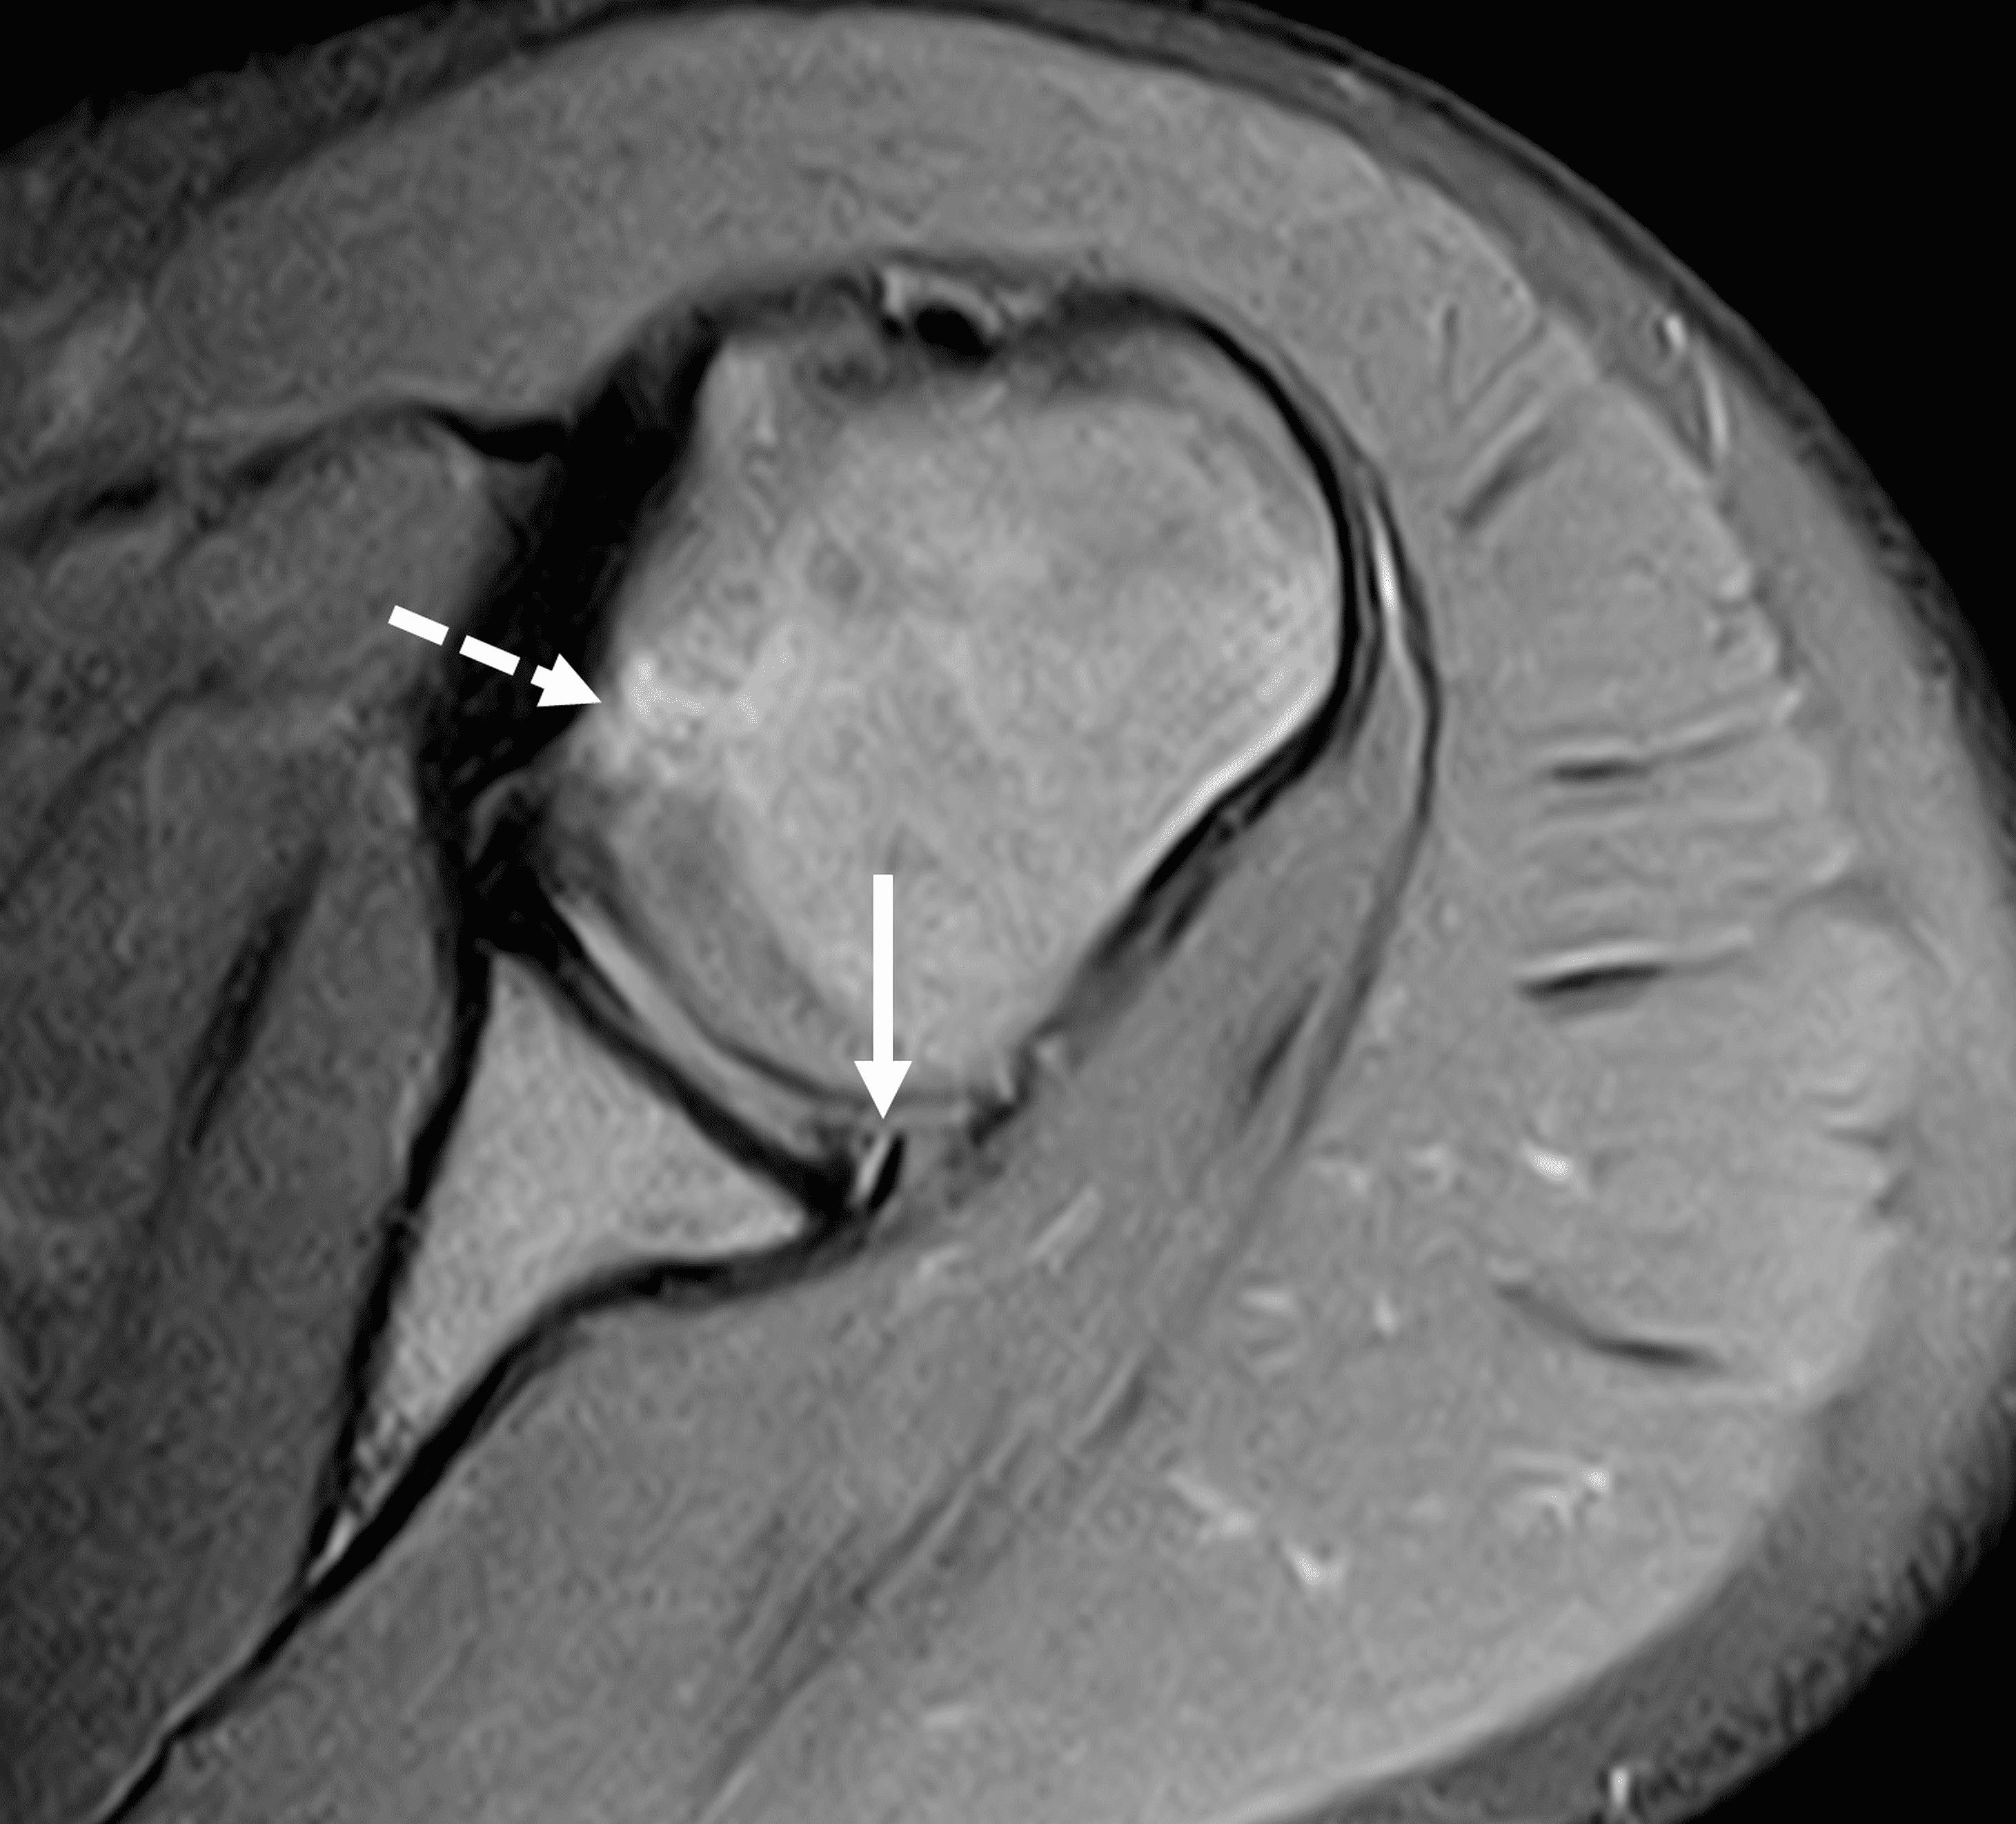

Figure 3: 18 year-old-female college softball player with acute left shoulder batting injury. (3A and 3B) Axial fat-suppressed proton-density-weighted images show a nondisplaced intrasubstance posteroinferior labral tear (solid arrows) and anteromedial humeral head impaction fracture with mild underlying marrow edema (dashed arrows).